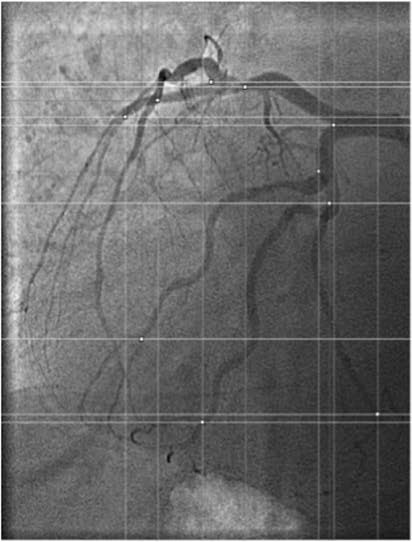

Location of the coronary arteries on the surface of the heart.Fig 1. Human coronary arteries.1

1. Gerrah, Rabin et al. "Localization of coronary bypass targets in hard-to-see coronary arteries." Journal of cardiothoracic surgery. 18,1 (2023): 290. Distributed under Open Access license CC BY 4.0, the original image's title was changed to "Human coronary arteries".